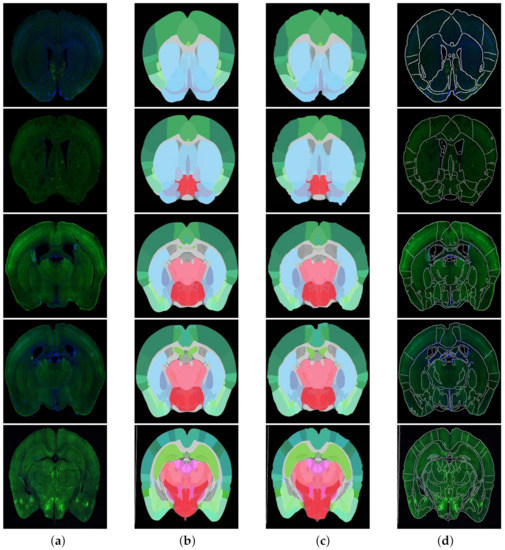

4.3.2. Modal Transformation

To better solve the problem of non-unified multi-modal image registration, using the modal transformation method to convert a multi-modal image into a monomodal image is an effective method. In this study, a Joint Enhancement of Multimodal Information image segmentation method was proposed. It segments the corresponding key features in the image to complete the modal transformation. To verify the performance of the proposed method, the U-Net network suitable for small samples was selected for comparison, and the results are shown in Figure 7. The commonly used evaluation indicators of PA, MPA, MIOU and FWIOU for image segmentation were used. The results were evaluated, and the performance analysis is shown in Figure 8.

The experimental results indicate that the U-Net network can accurately segment the ATA images with obvious features and less noise. As for some brain slice images with no obvious features and a lot of noise, they could not recognize the key features or achieve satisfactory segmentation results. The JEMI network proposed in this study trains two multi-modal images together, and, by fusing the input multi-modal information, it can both promote and enhance the learning of key features and also restrict the influence of marker neurons to achieve a better effect of modal transformation ultimately.

Figure 7. Results for Brain Slices and ATA using different modal transformation methods; the original Brain Atlas and original brain slices (middle); the effect of using the U-net method for modal transformation (left); the effect of using the JEMI method for modal transformation (right). It was obvious by comparison that the JEMI method was better.